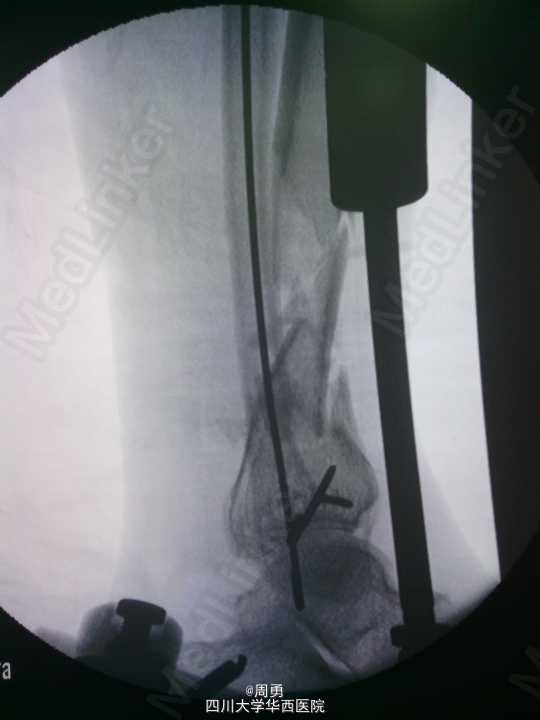

闭合穿针复位腓骨在开放性骨折中应用和意义

某些腓骨骨折常无需处理,但在开放性骨折一期处理创面同时,为了达到恢复肢体长度、条件允许情况下最大可能复位骨折、简化二期手术目的,某些时候复位腓骨并闭合穿克氏针对骨折复位和固定会有一定帮助,选几年前2个博士住院总期间X片示意,欢迎大家交流。